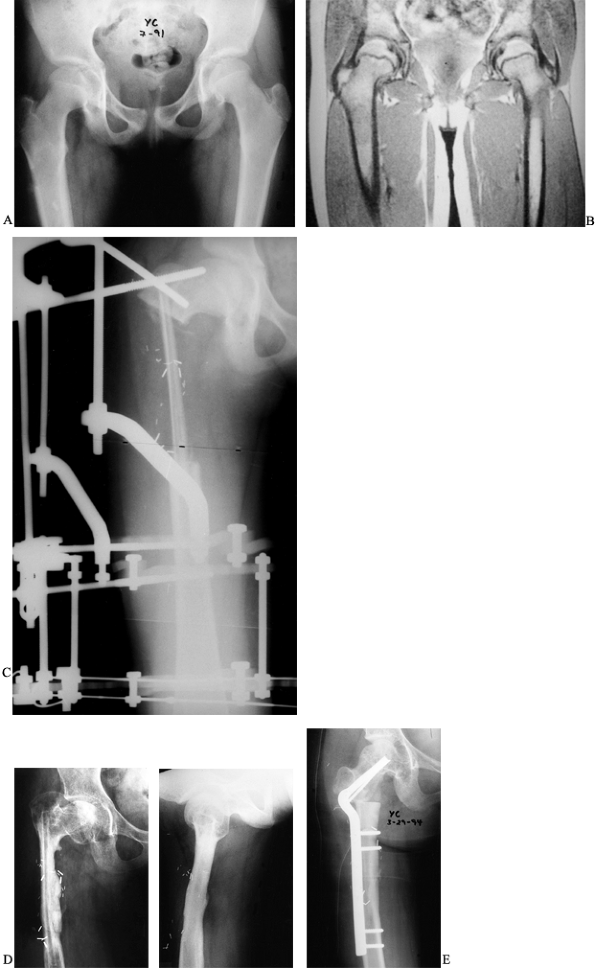

A low-grade chondrosarcoma was treated by wide local excision, leaving

a defect measuring 14 cm in the proximal femur. The defect was

reconstructed using a vascularized fibula doweled into the recipient

femur and external fixation to stabilize the graft. The graft healed

uneventfully, but the patient later required a valgus intertrochanteric

osteotomy to correct a resultant varus deformity of the proximal femur.

Figure 36.2. A: Radiographs of a 10-year-old girl demonstrate a lucency and periosteal reaction in the right proximal femur. B: An MRI of the femur further delineates the lesion in the proximal shaft. C:

Postoperative radiograph revealing the fibular graft and the external fixator in place. Note the doweling of the graft into the femur. D: Anteroposterior and lateral radiographs 3 years postoperatively reveal incorporation and hypertrophy of the graft but a varus deformity of the femoral neck. E: A 50° intertrochanteric valgus corrective osteotomy performed to improve neck shaft angle.  |